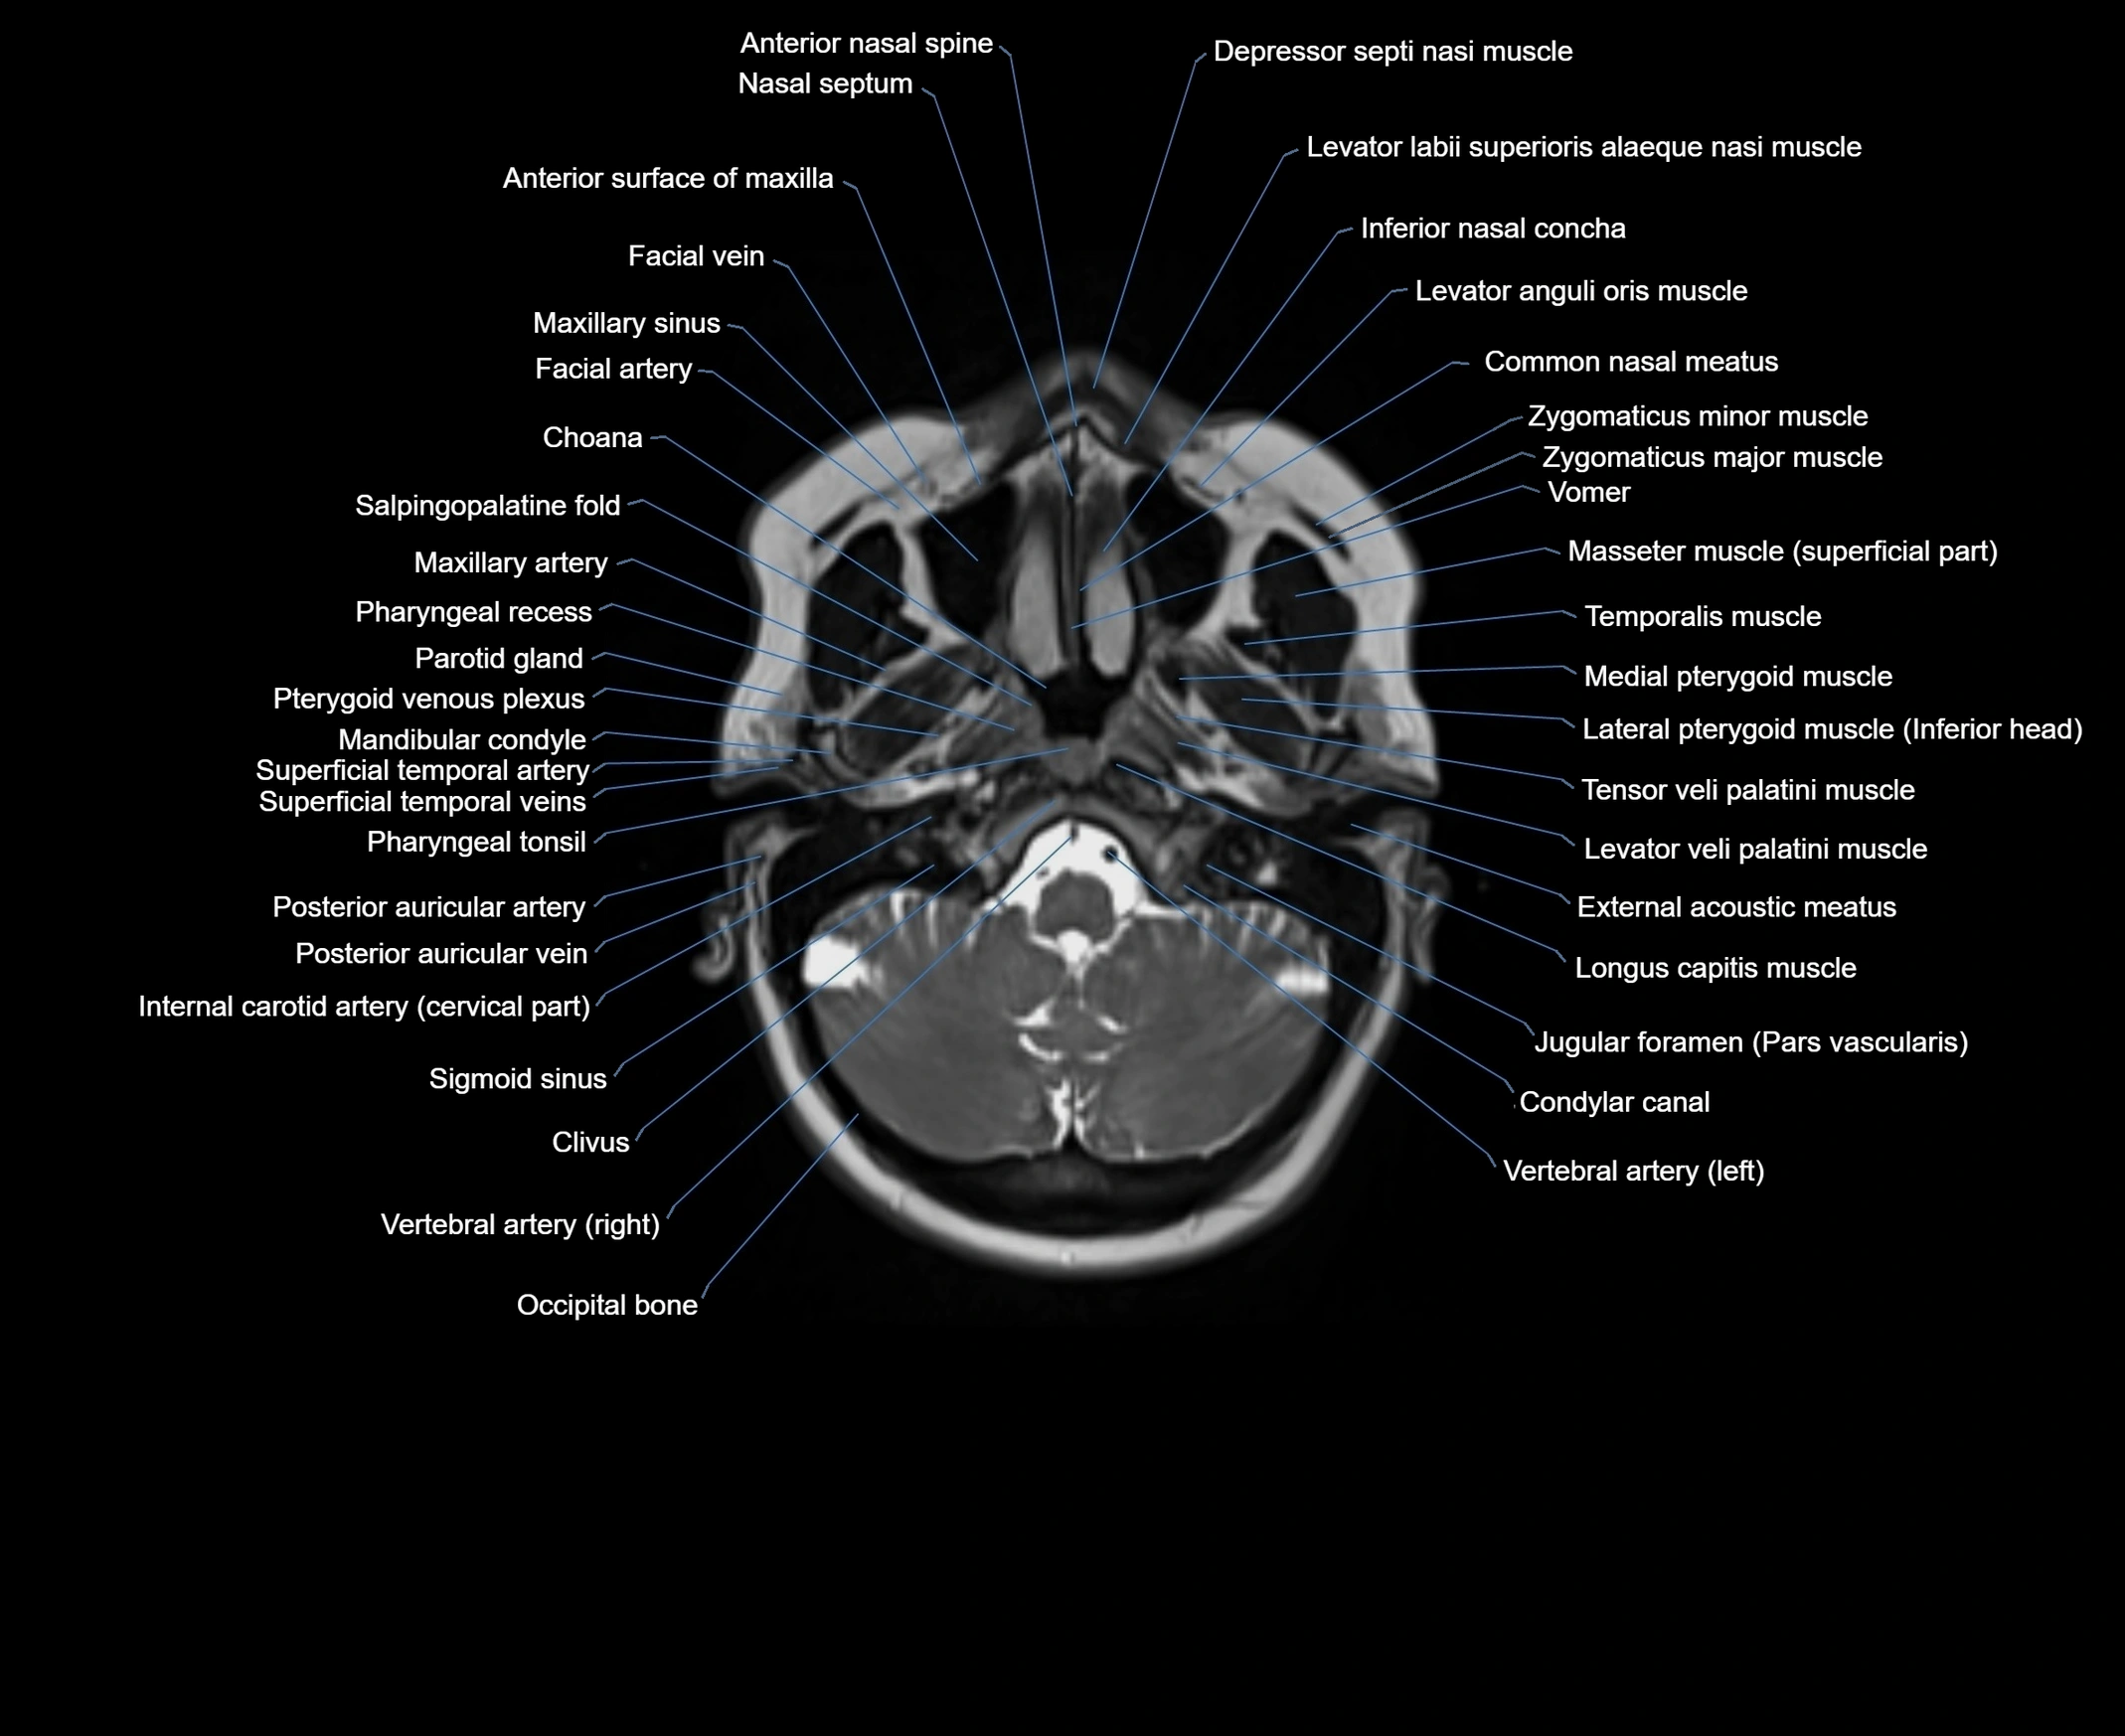

- Choana

- Clivus

- Common nasal meatus

- Condylar canal

- Internal carotid artery (cervical part)

- Mandibular condyle

- Occipital bone

- Parotid gland

- Pharyngeal recess

- Pharyngeal tonsil

- Posterior auricular artery

- Posterior auricular vein

- Pterygoid venous plexus

- Scapula

- Superficial temporal artery

- Superficial temporal vein